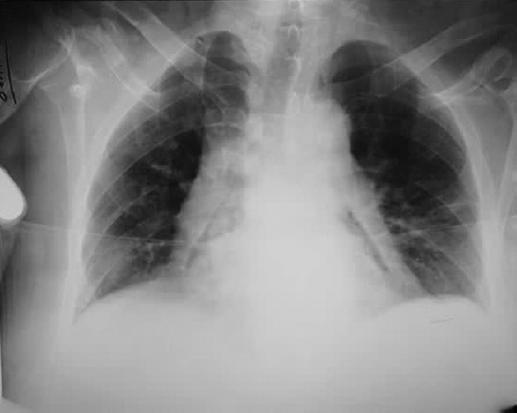

Dentro de los estudios de gabinete, la radiografía de tórax mostró neumopericardio (Fig. 1) y la tomografía computarizada (TC) toracoabdominal una comunicación fistulosa en la curvatura menor al pericardio con presencia de neumopericadio, sin aire libre abdominal (Fig. 2). Decidimos realizar una endoscopia gastroduodenal, con hallazgo de una úlcera gástrica en el cuerpo anterior gástrico y penetración al mediastino, con visualización del movimiento cardiaco a través del pericardio, sin evidencia de sangrado activo (Fig. 3). Posteriormente se realizó un ecocardiograma, sin evidencias de compromiso del gasto cardiaco.

Figura 1 Radiografía de tórax que muestra ensanchamiento mediastinal y una banda radiotransparente que envuelve al pericardio.